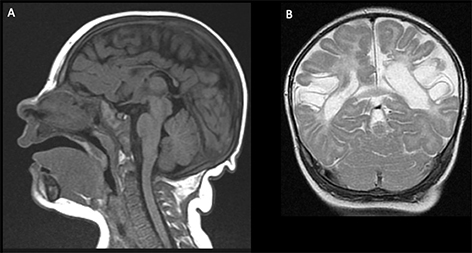

Acute phases of fetal stroke, such as in case of congenital heart disease or twin-twin transfusion syndrome (TTTS), may only rarely be detected prenatally. Fetal stroke often manifests with the chronic features of unilateral ventriculomegaly and volume loss with or without associated hemorrhage (Figures 1 and 2).

Figure 2. Three-day-old girl with chronic encephalopathy. Pregnancy complicated by maternal HELLP (H: Hemolysis, EL: elevated liver enzymes, LP: low platelet count) syndrome. Sagittal T1- (A) and coronal T2-weighted images (B) show microcephaly and bilateral chronic MCA-territory infarctions. Case courtesy of Dr. Tamara Feygin, Department of Radiology, Children’s Hospital of Philadelphia.